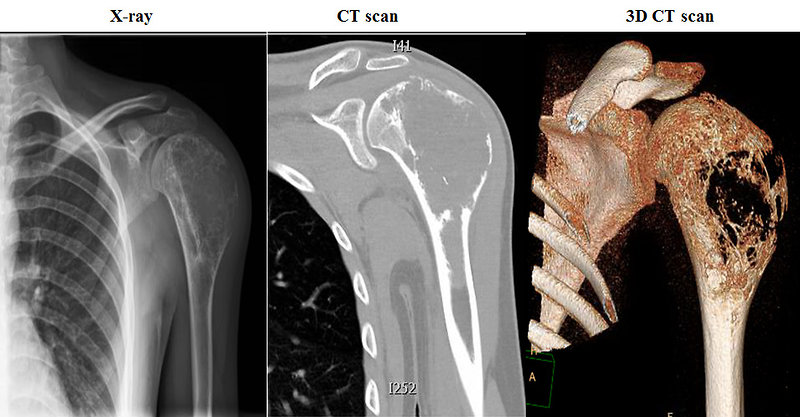

- Рентгенография . Бърз и прост диагностичен метод, в някои случаи помага незабавно да се идентифицира тумор. Ако има съмнение за метастази в белите дробове, се прави рентгенова снимка на гръдния кош.

- Магнитен резонанс (MRI) и компютърна томография (CT) помагат за по-подробно изследване на тумора и откриване на растеж в съседни тъкани.

- Образни изследвания, които включват рентгенови лъчи на костите, PET сканиране, MRI и CT сканиране на костите